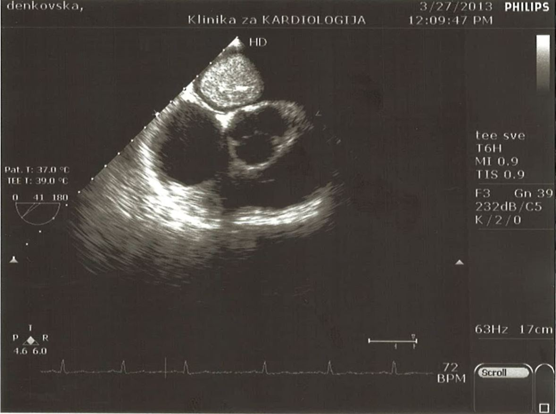

Transthoracic echocardiogram (Figure 2) (Figure 3) revealed a large atrial mass occupying the majority of the left atrium with dimensions 2,97 x 4,28cm with no obstruction of the mitral valve orifice. Transesophageal echocardiography (Figure 4) (Figure 5) confirmed presence of a large mass in the left atrium attached to the interatrial septum without prolaps of the tumour through the mitral valve. After coronary angiography and completion of preoperative dignostics, patient was transferred in another institution for surgical treatment. After surgical removal of the cardiac tumour, we received the histopathological material (Figure 6) which confirmed the diagnosis of cardiac myxoma. We continued with follow up of the patient by echocardiography control right after surgical treatment, as well as after 3 months, after 6 months, and after 12 months with no signs of tumor recurrence. She feels well and continues to take regularly antihypertensive drugs.7–9

Figure 4 TEE image of the left atrial myxomas.

Figure 5 TEE image of the left atrial myxoma with no visible obstruction the mitral valve orifice.